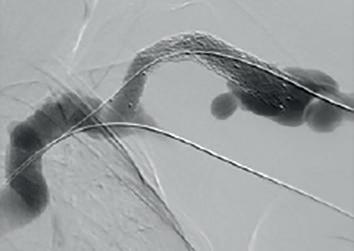

Example procedural outcome: treatment of Bond’s patient with a left brachiocephalic AVF that presented with a stenosis at the cephalic arch with aneurysmal segment.

(A) Fistulogram taken preintervention and (B) after deployment of WRAPSODY to treat. (C) Fluoroscopy of treated segment at 18 months (D) and patient’s arm at time of presentation

When asked why he chose Wrapsody CIE, he notes that, due to the anatomical anomaly present in this patient, no other endoprosthesis would have yielded a positive outcome. In addition, he indicates that the device’s design, specifically its tactile feel, made it a good treatment option. For Bond, the whole process was “very, very intuitive” and use of the device was “very straightforward”. As for the patient, he notes that she tolerated the procedure quite well: “The next day, the patient was achieving all of her dialysis

goals, and her pain was resolved overnight. She is due for her three-year angiogram this month— she has not had any issues with dialysis.”